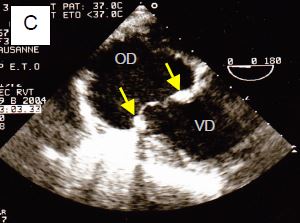

Figure 11.159 : Chirurgie de la valve tricuspide. A : IT résiduelle mineure après une plastie selon De Vega pour RAA ; la valve mitrale a été remplacée par une prothèse mécanique (flèche jaune). B : anneau de Carpentier (flèche jaune) et réimplantation de cordage (flèche verte) pour rutpture traumatique du feuillet antérieur (même cas que Figure 11.117A et 117B). C : remplacement de la tricuspide par une bioprothèse, dont voit bien l’anneau (flèches) et deux feuillets.